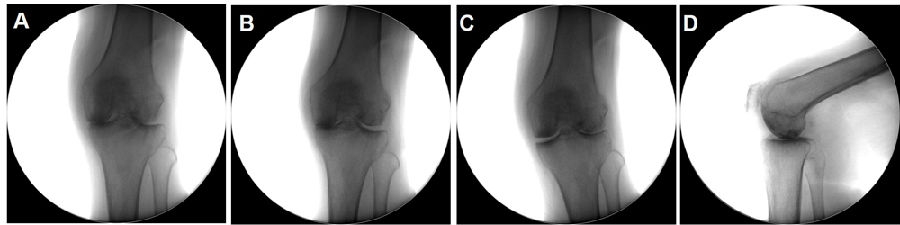

Case3:一期Bi-UKA治疗双间室OA

术前动力位片

术前透视。A.模拟负重位B.内翻应力位C.外翻应力位D.侧位

手术切口与暴露。A.膝前正中切口B.髌旁内侧入路C.内侧、外侧股骨髁磨损,ACL功能正常

内侧单髁置换。A.截骨完成B.安装内侧假体,等待骨水泥凝固C.假体安装完成

外侧单髁置换。A.按照外侧假体,等待骨水泥凝固B.内外侧单髁假体安装完毕C.切口及引流